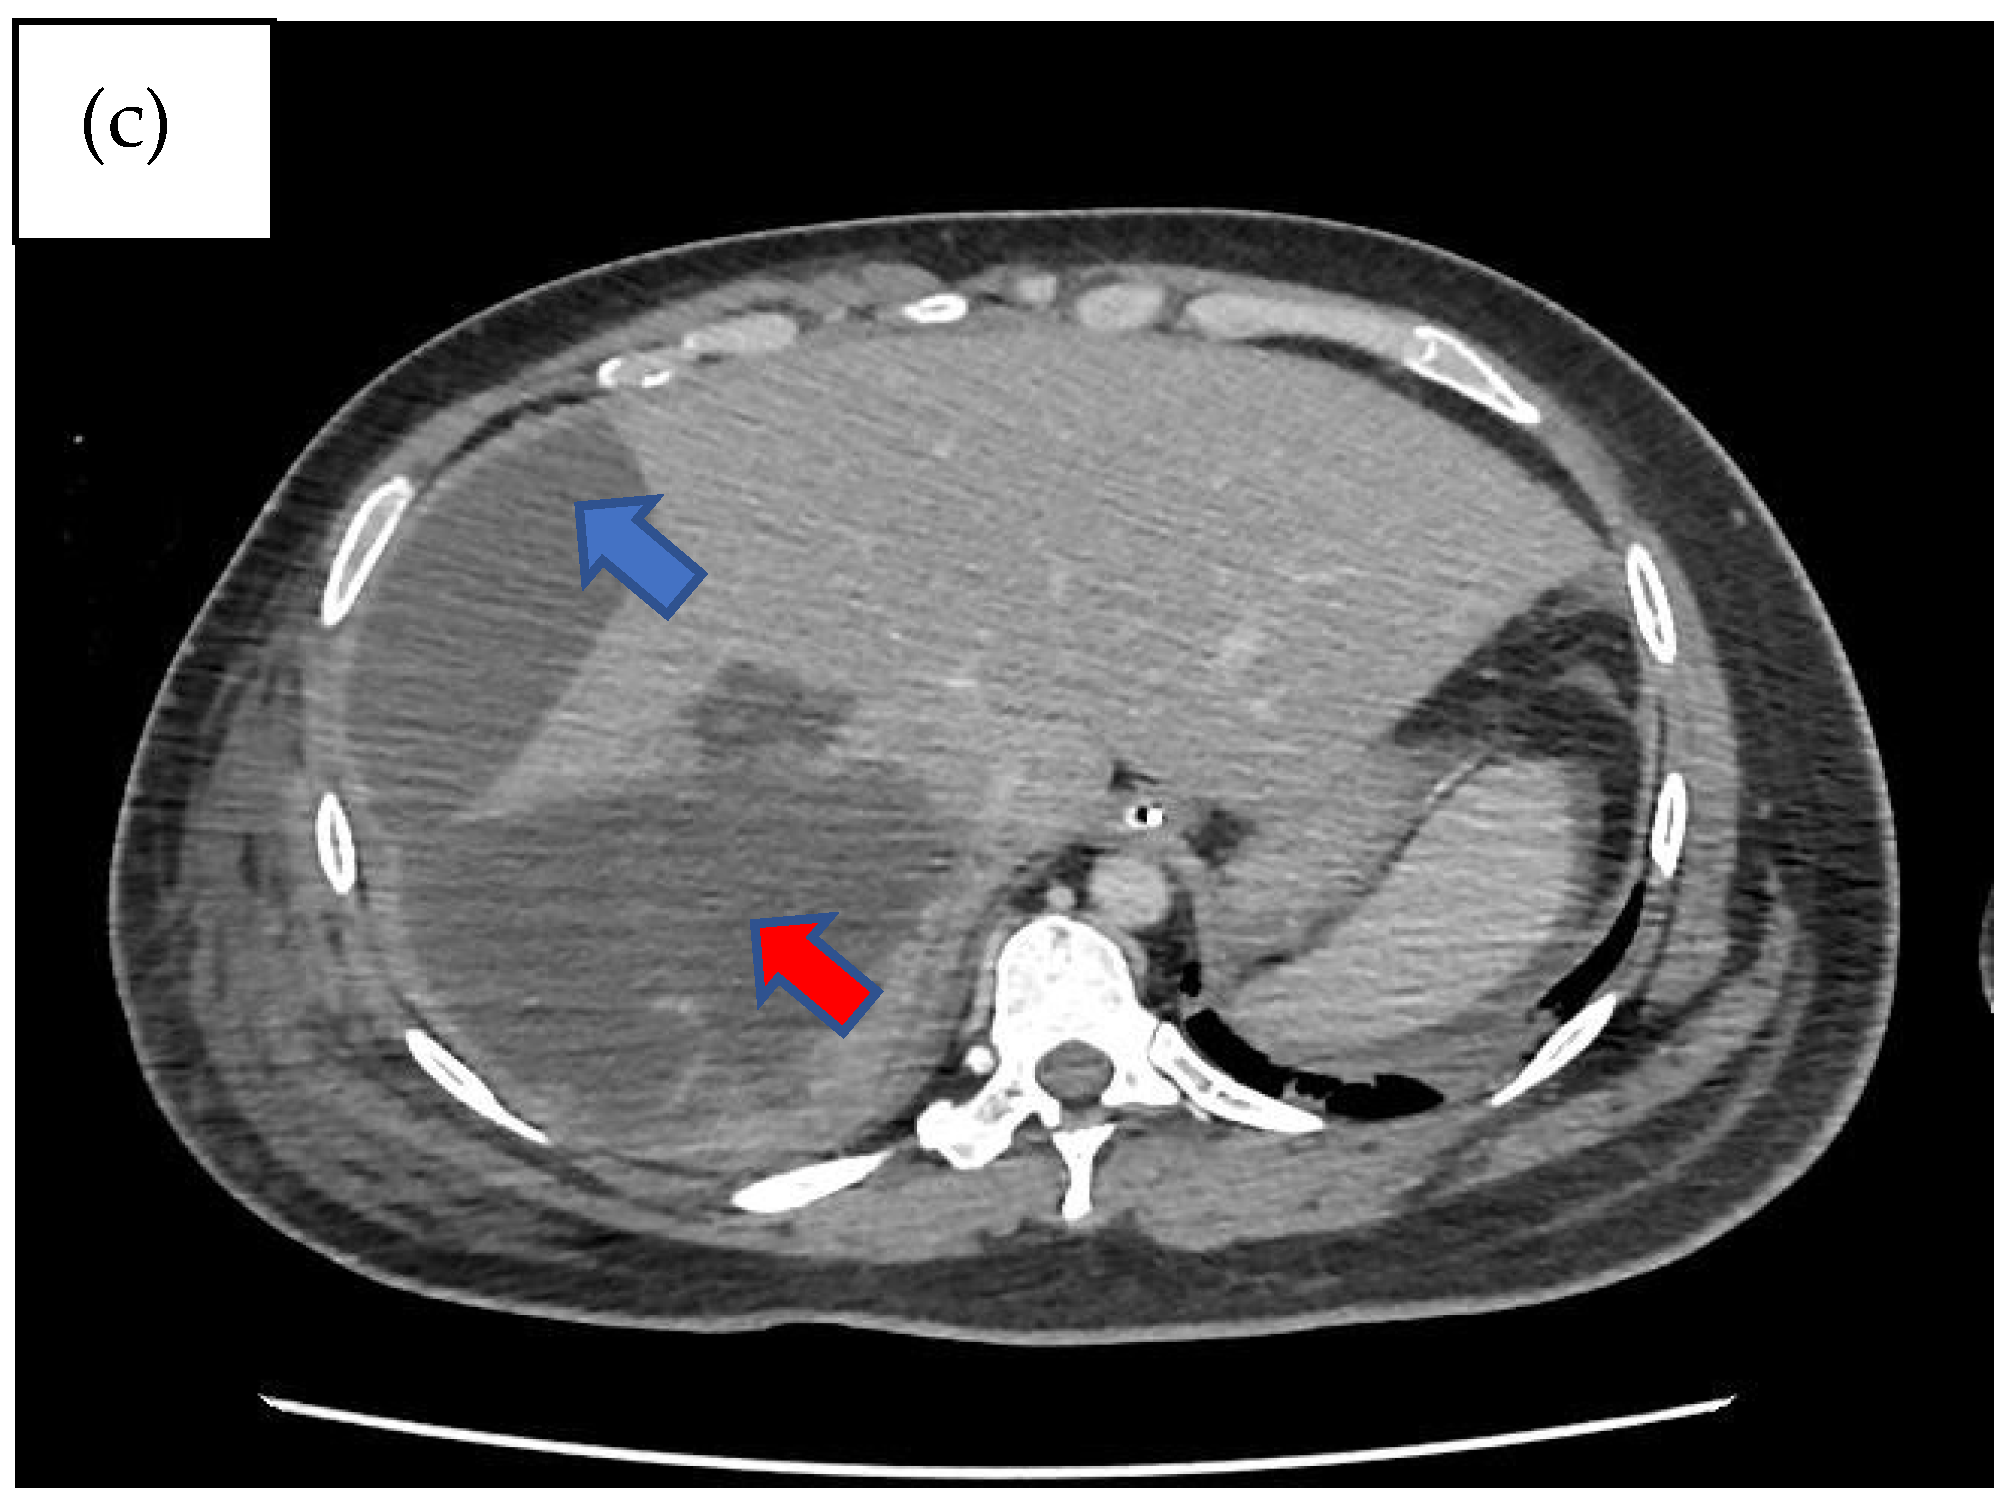

Three days following the laparotomy, the patient developed ventilator-associated pneumonia and intra-abdominal sepsis and was treated empirically with fluconazole and piperacillin–tazobactam. Repeated imaging of the abdomen was carried out in view of a poor response to antimicrobial therapy and showed the formation of biloma (Figure 1). A percutaneous subdiaphragmatic drain was inserted under computed tomography (CT) guidance by the interventional radiology team to facilitate drainage, despite being able to drain only a minimal amount, and the drain was dislodged after three days. In view of ineffective percutaneous drainage with worsening intrabdominal sepsis despite one week of adequate antimicrobial therapy, upon discussion with the hepatobiliary team, we decided to proceed with a hemi-hepatectomy for the removal of the biloma.

Imaging remains the gold standard for diagnosing bilomas, with ultrasound (US) often being the initial imaging modality used. Bilomas typically appear as well-defined hypoechoic fluid collections within the abdomen that vary in size and shape, ranging from small localized areas to larger, more extensive masses. It also has the capability of detecting the content within the biloma by showing a variety of findings ranging from well-defined collections in the liver parenchyma to extensive fluid collections across the abdomen [8]. Notably, US findings show heavily loculated bilomas are often linked to infection [9]. CT imaging can help identify the overall structure of the biloma, delineating clear margins that can be either encapsulated or non-encapsulated [10]. While CT imaging offers a more intricate view of bilomas, it lacks the capability to conclusively distinguish among various potential diagnoses, including seroma, abscess, lymphocele, liver cyst, hematoma, and pseudocyst [11]. Consequently, additional imaging modalities such as magnetic resonance (MR) imaging or hepatobiliary cholescintigraphy may be necessary to help validate the diagnosis. Direct sampling of the biloma together with these imaging techniques will also help with the diagnosis [10]. In T1-weighted images, bilomas will display low signal intensity, whereas in T2-weighted images, high signal intensity is seen [12]. Furthermore, MR imaging can help to define the characteristics of a biloma. While contrast infrequently penetrates the biloma, rim enhancement and septations occasionally occur due to reactive inflammation and infection [12]. Hepatobiliary cholescintigraphy serves as a highly efficient non-invasive imaging technique for diagnosing and strategizing treatment for bilomas by utilizing a radiotracer known as Tc-99m iminodiacetic acid, which is commonly referred to as hepatobiliary iminodiacetic acid (HIDA) imaging [10,13]. HIDA imaging exhibits a high level of sensitivity in detecting bile leaks [13]. Nonetheless, it lacks the ability to offer detailed imaging of the surrounding anatomical structures. Single positron emission computed tomography (SPECT) is another imaging technique that has the ability to furnish more intricate imaging of potential leak locations, proving particularly valuable in planning percutaneous image-guided drains [10]. Endoscopic retrograde cholangiopancreatography (ERCP) and percutaneous transhepatic cholangiogram (PTC) can be considered not only for diagnostic tests but also may offer some degree of intervention either percutaneously or endoscopically [13]. Other minimally invasive investigations available are CT-guided sampling technique and US-guided sampling technique. However, these techniques require laboratory assistance to analyse the sample collected [10]. In our case, CT imaging was sufficient to give us the information we need. The initial CT imaging (Figure 1) revealed a rim-enhancing lesion surrounding the biloma, suggesting a potential infective biloma. However, we did not perform a biopsy and or staining hepatic tissue during the hemi-hepatectomy to definitely confirm that Rhodotorula mucilaginosa originated from the biloma itself. This limitation underscores a key aspect of our study, highlighting the need for further investigations to establish a direct link between the presence of Rhodotorula mucilaginosa and the biloma. MR imaging was not performed in this patient which shows another limitation in this case. MR imaging might indicate presence of septations within the biloma and this might be the reason why percutaneous drainage failed in this patient.

Figure 1. Computed tomography scan of the abdomen non-contrasted phase showing heterogenous areas consisting of hematoma and laceration at segments V, VI, VII, and VIII extending down to the subhepatic region (red arrow). Inferiorly, it extends down to the hepatic flexure, just lateral to the right pararenal space. Another subcapsular collection was seen adjacent to right liver lobe (blue arrow): (a) coronal view, (b) sagittal view, and (c) axial view, with findings as aforementioned.